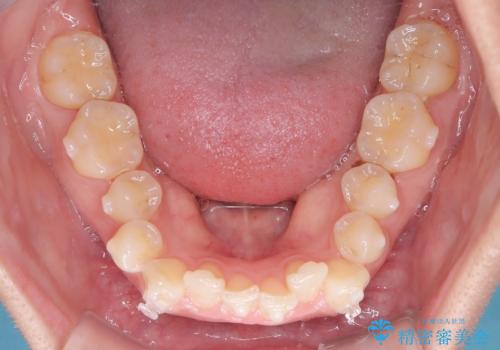

- 前歯のガタガタが気になるとのことでご相談いただきました。診察すると、歯列のスペースが不足し、前歯が重なっている状態でした。抜歯をせずに整えるため、歯と歯の間をわずかに削るIPR(歯列幅径削除)と、奥歯を後方へ動かす遠心移動を組み合わせてスペースを確保しながら並べる治療計画を立てました。

インビザラインを用いて歯を少しずつ移動させながら、IPRで微調整を行い、スペースを確保しました。また、奥歯を遠心移動させることで、前歯を自然な位置に並べることができました。治療後は、「ガタガタがなくなり、スムーズな歯並びになった」と患者様にもご満足いただきました。